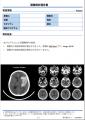

[画像2:

DoctorNET Heuron CTSのレポートフォーマット(高吸収領域の検出時)